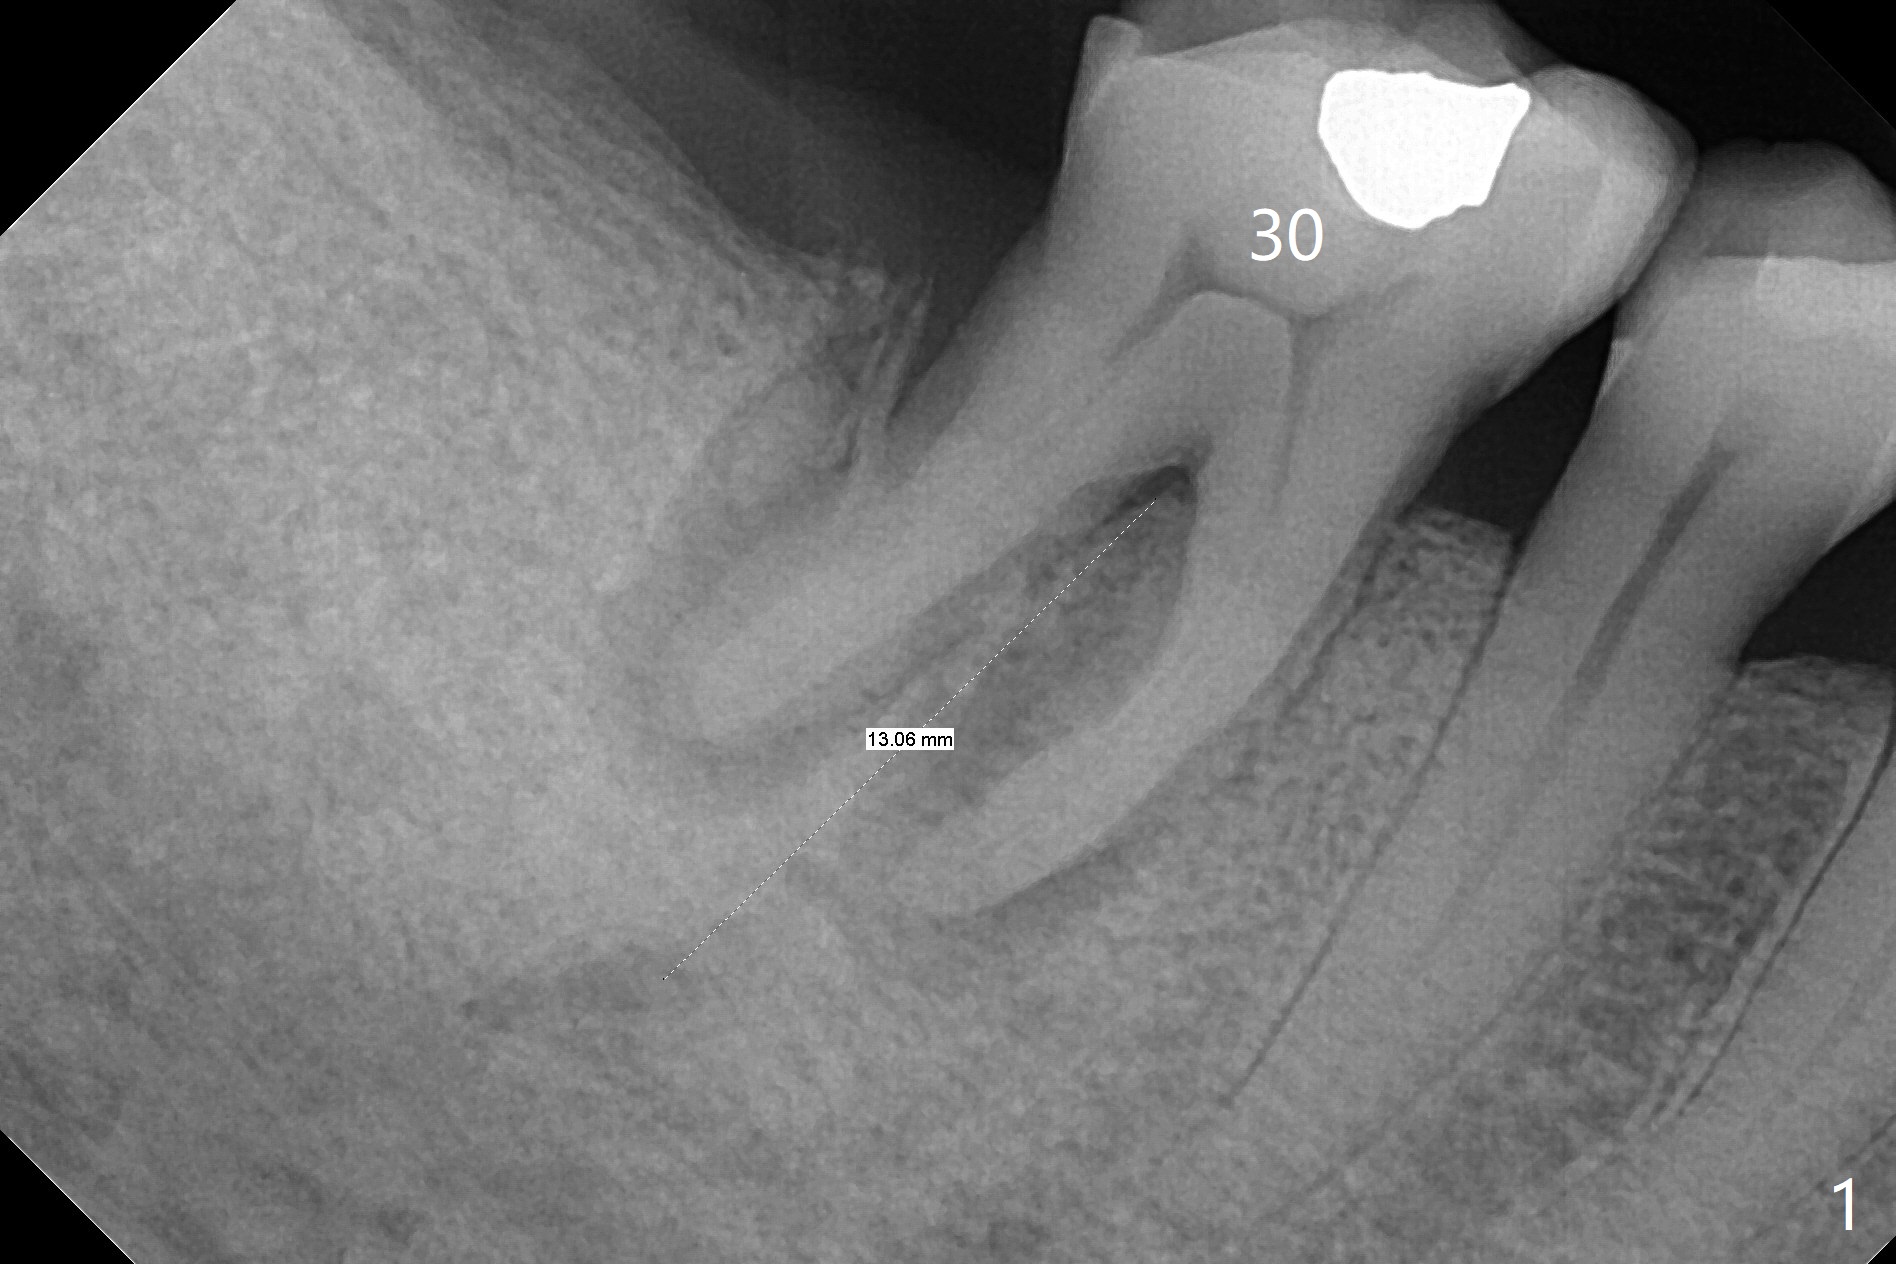

A 71-year-old woman (bruxer) wants to remove the tooth #30 (occlusal trauma, possible root fracture) for implant following the one at #14 (Fig.1). IBS abutment screw tends to loosen in functioning if the implant is placed too deep and/or off the longitudinal axis. If these two conditions are not controlled well, switch to a large tissue-level implant. A drawback of placing the implant in the septum is that the mesial margin of the abutment (Fig.2 pink) is subcrestal. If the implant is placed in the mesial socket (Fig.5 red line), the imagined abutment margin plane (white line) is parallel to the mesiodistal crests. Initial osteotomy entry point in the mesial socket and trajectory should be adjusted intraop (compare Fig.6 and 7) so that the apex of the implant will not be too close to the apex of the tooth #29 (to avoid truncating the neurovascular supply to the tooth (Fig.6 red arrowheads)) at the same time the abutment inclination is not too compromised (Fig.7). To prevent pressure upon the buccal (Fig.4 B) plate, osteotomy should be slightly lingual and/or the diameter of the implant is to be < 7 mm. Use a 3 mm unipost for provisional and probably 5 mm one for definitive restoration. Apply bonding to the post if the implant is 6 mm or less. The provisional margin should be wide and deep for deep margin and easy impression later. Use IS drills with 4 mm stopper for osteotomy if the septum is absent. Prepare Rongeur and surgical handpiece to remove the remaining septum if needed. Be wary of the distally curved root tip of #29. In fact there is a mesiodistal crack line (Fig.8 arrowheads) with buccal recession (Fig.9, 2 weeks preop).